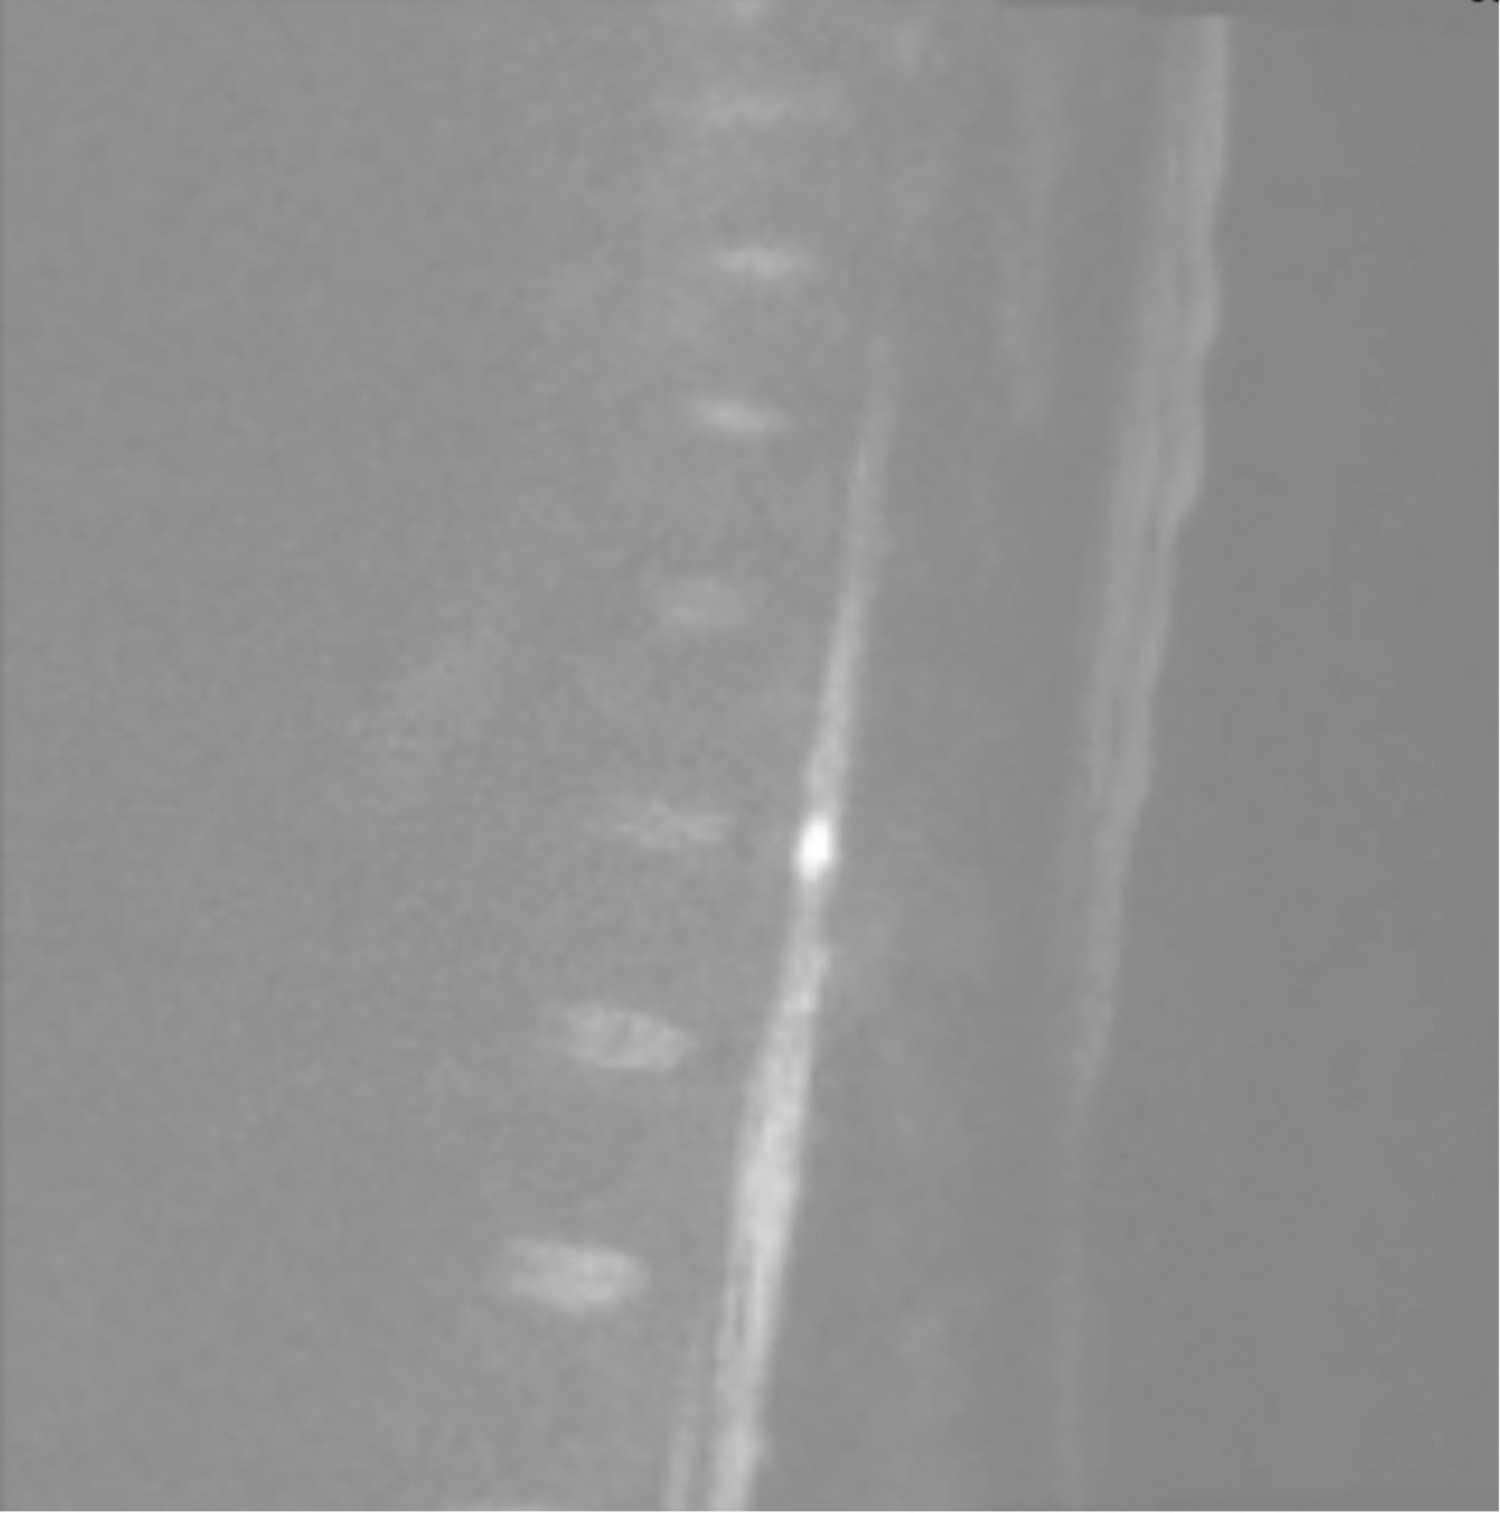

The patient could not be mobilised without assistance and had already been diagnosed with urinary retention in the emergency department. She had now also developed constipation. A head MRI on day 5 showed no signs of acute cerebral infarction. In consultation with the on-call neurologist, an MRI of the entire spinal column was performed on day 6, revealing T2 high-signal changes at the Th11–Th12 levels, measuring 5 cm × 0.6 cm (Figures 1 and 2), consistent with either infarction or myelitis.